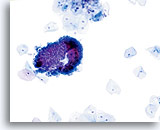

Adenocarcinoma in situ

Variably sized, crowded, hyperchromatic groups of cells are seen on screening power which warrant a closer inspection. 20x